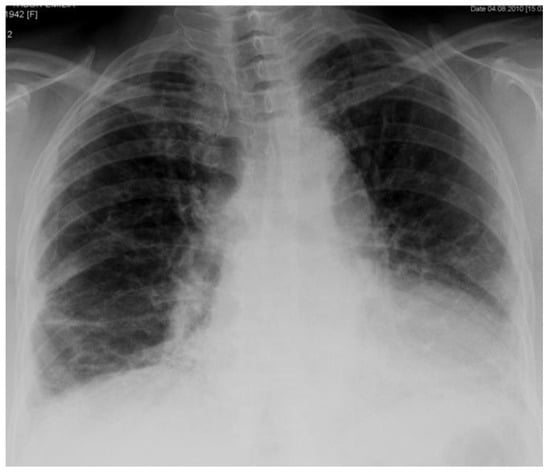

2. Case Report